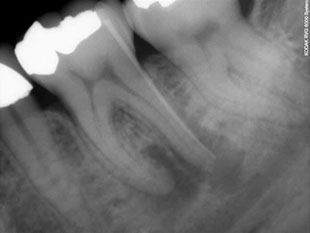

All'esame radiografico, sia l'Ascesso che il Granuloma sono rappresentati da  un'area di ridotta densità ossea, visibile come un'areola scura in prossimità dell'apice radicolare.